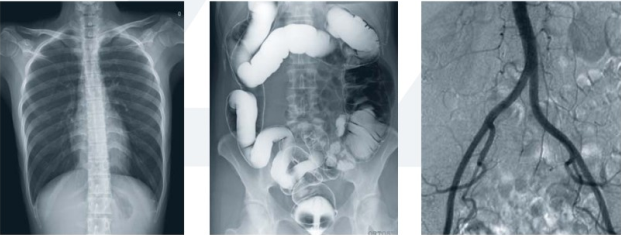

隨著醫療行業的發展,行業創新產品不斷涌現。在放射影像領域,醫院放射影像科的基本設備—數字X攝影系統(DR)近年來也在不斷更新換代,新一代多種功能動態DR成為行業發展新趨勢,其“一臺機器、多種用途”成為醫院提升設備使用率和看病效率的有力武器。那么動態DR有哪些優勢呢?

動態DR的顯著特點是多項功能復合。隨著影像技術的快速發展,新一代DR不再是只能實現簡單的拍片功能,而且擁有透視、造影等多項復合功能。

動態DR可以實現透視后點片,通過透視消除靜態DR的盲拍缺陷,對病灶直接快速定位,實現精 準診斷。

動態DR擁有可視化造影功能,在進行造影檢查時,成像幅面大,無需移動球管,一個幅面就可以連續觀看造影劑的流向以及造影部位的全部情況,在造影過程中還能實現900萬像素實時點片,為醫生的臨床診斷提供優異的影像數據。

動態DR能實現全身拼接,適用于全脊柱、全下肢攝影,輔助脊柱畸形的矯形治療、康復檢查,為臨床提供高精度圖像。

PLD9000A動態平板DR既能實現數字化攝影、數字化透視,又能將數字化胃腸功能、數字化造影功能整合于一體,革新的動態平板探測器作為全新的數碼載體,可實現高質量和高幀速透視。

動態平板DR的透視和攝影均使用同一高效動態平板,提供無與倫比的臨床應用范圍,包括幾乎所有的普放檢查、胃腸鋇餐檢查和血管造影檢查等。

高效動態平板在透視過程中可以達到每秒30幀,使動態透視獲得媲美平板攝影的圖像質量與尺寸,更有利于臨床診需求。

采用大尺寸動態平板技術,大范圍覆蓋檢查面積,對任何結構部分進行檢查時,可提供比16英寸影像增強器多50%的覆蓋尺寸,是傳統影像增強器無可比擬的功能;同時,透視檢查時不需要對病人重新定位便可觀察到足夠大的人體器官組織。